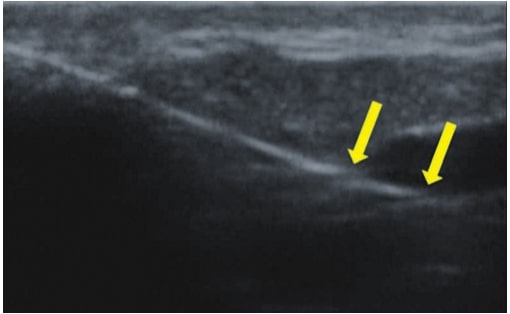

Die Doppler-Sonographie ermöglicht die Darstellung großer Gefäße und Perforatoren, die sich meist in tieferen Bereichen des subkutanen Gewebes befinden. Mit klassischem Ultraschall lassen sich kleinere Gefäße jedoch nicht darstellen. Für die Darstellung kleinerer Gefäße, die oberflächlich unter der Epidermis und im oberen subkutanen Gewebe liegen, wird HFU eingesetzt. Mit Sonden über 20 MHz Frequenz erhält man hochauflösende Ultraschallbilder, auf denen Objekte kleiner als 0,1 mm unterscheidbar sind. Mit zunehmender Auflösung nimmt jedoch die Eindringtiefe ab. Je nach Sonde und Gerät beträgt die maximale Eindringtiefe etwa 20–30 mm. Diese Eindringtiefe bei gleichzeitig hoher Bildauflösung ermöglicht die Beurteilung sehr kleiner Gefäße. HFU erlaubt die genaue Bestimmung des Verlaufs und der Lage kleiner Gefäße in der Haut, was entscheidend für die Wahl der Verschlussmethode und die Planung des Eingriffs ist. Oft sind an der Hautoberfläche nur wenige Gefäße sichtbar – erst durch die Ultraschalluntersuchung lässt sich die tatsächliche Anzahl und der Verlauf feststellen. Für einen erfolgreichen Verschluss muss das gesamte Gefäß behandelt werden, nicht nur der sichtbare Teil, da sonst eine schnelle Rekanalisation erfolgt (7). Häufig ändert das an der Haut sichtbare Gefäß seinen Verlauf, wird gewundener und zieht in tiefere Hautschichten (8). HFU ermöglicht zudem die Darstellung der Perforatoren zwischen kleinen Gefäßen und die Messung grundlegender Parameter wie Durchmesser, Wandstärke, Tiefe und Blutfluss (6). Mit der 40-MHz-Sonde von Ultrasonix kann auch der Blutfluss mittels Farbdoppler visualisiert werden.

Dieses Verfahren überträgt intravaskuläre Techniken aus der Behandlung großer oberflächlicher Venen auf die Mikroebene. Ein Laserfaser wird in das Gefäß eingeführt und koaguliert das Gefäß mit Laserenergie (7,11). HFU ist für die korrekte Durchführung unerlässlich, da es Verlauf, Anatomie, Faserposition, Koagulation und Erfolg des Eingriffs überwacht.

Diese Arbeit behandelt die Anwendung von HFU zur Darstellung und zum Verschluss kleiner Venen, d. h. Teleangiektasien und retikulärer Venen. Hochfrequenzsonden >20 MHz ermöglichen die Ultraschalldarstellung der Gefäße in der Dermis und subkutanen Gewebe, was mit klassischen Sonden nicht möglich ist. Ultraschall erfüllt die Erwartungen von Chirurgen und Phlebologen, die bisher keine Möglichkeit hatten, kleine Gefäße zu beurteilen. Traditionelle Durchlichtgeräte waren nur begrenzt einsetzbar, da sie nur oberflächliche Gefäßverläufe zeigten (12). Die Beurteilung von Verlauf, Durchmesser und Tiefe ist entscheidend für die Wahl der Therapie, steigert die Effektivität der Eingriffe und reduziert Komplikationsrisiken. Beim Laser entscheidet das Ultraschallbild über die Wahl des Lasers und die Eingriffsparameter (7). HFU ist auch ein wichtiges Werkzeug zur Überwachung von Eingriffen. Ohne Ultraschallkontrolle wären mikroendovaskuläre Eingriffe oder Mikrosklerotherapie praktisch unmöglich, da sonst ein hohes Risiko für Nekrosen durch Fehlinjektionen besteht.